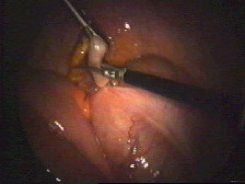

Presentación y tracción del apéndice

Disección del apéndice

Presentación y colocación de la ligadura

Control de hemostasia